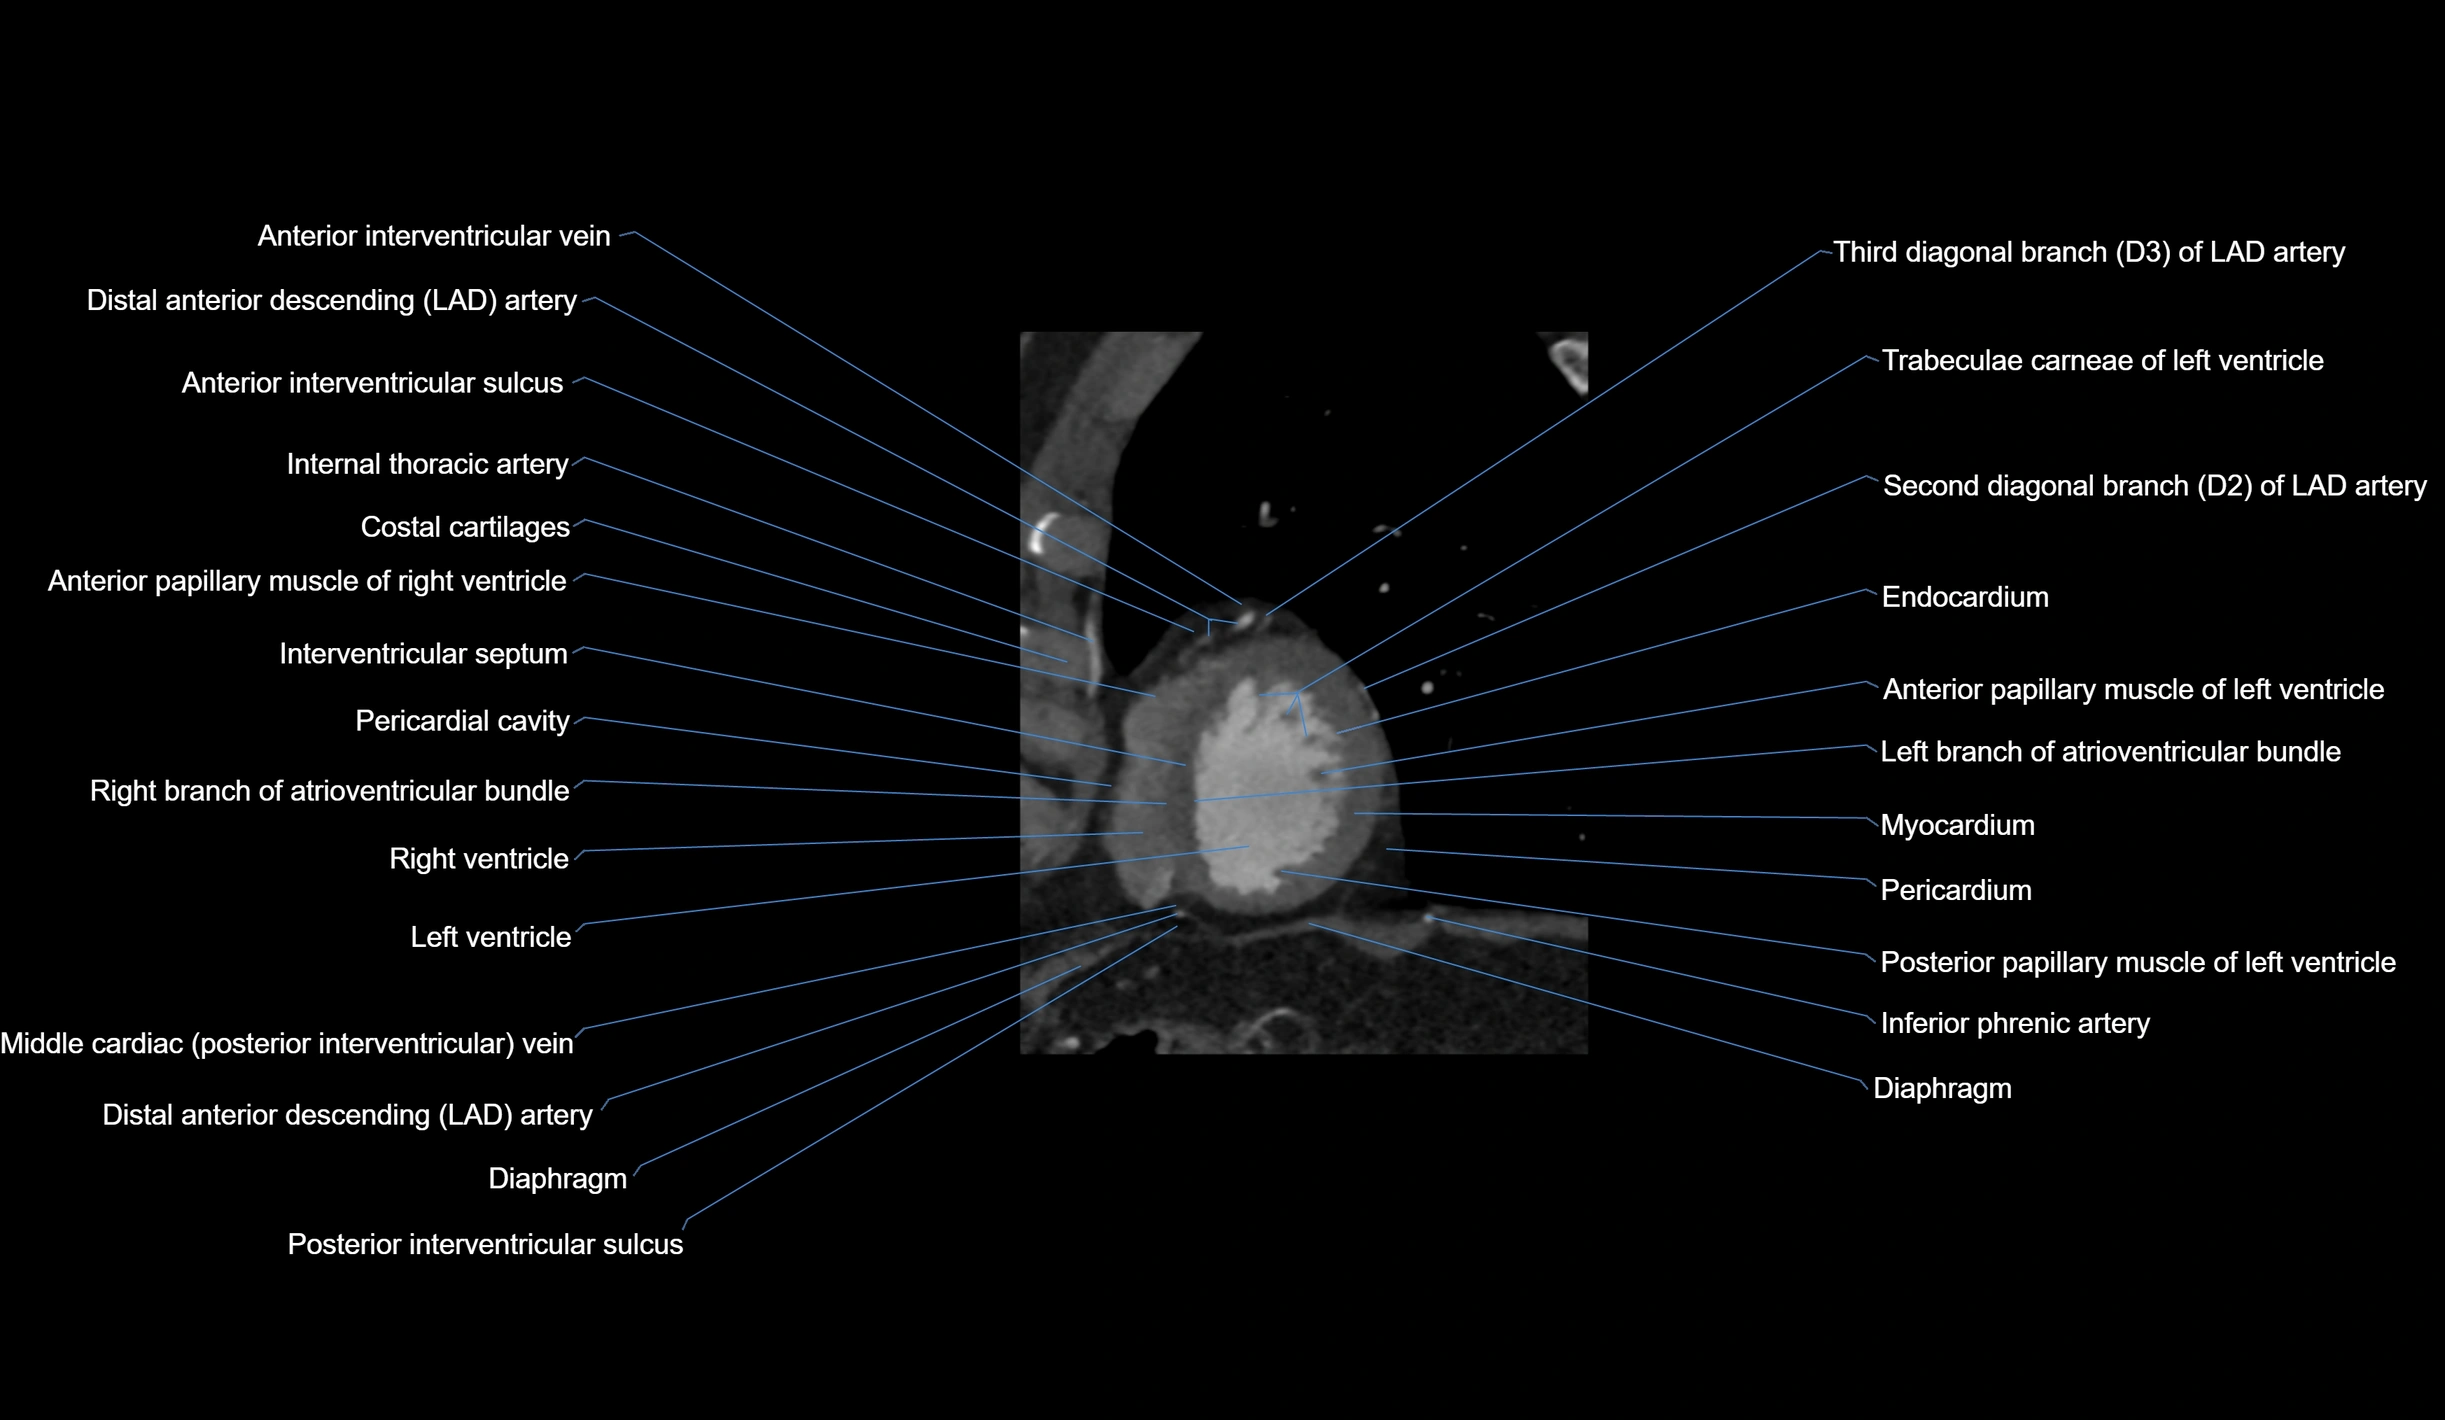

- Anterior interventricular sulcus

- Anterior papillary muscle

- Costal cartilages

- Diaphragm

- Distal left anterior descending artery (dLAD)

- Endocardium

- Inferior phrenic artery

- Interventricular Septum

- Left branch of atrioventricular bundle

- Myocardium

- Pericardial cavity

- Pericardium

- Posterior interventricular sulcus

- Posterior papillary muscle

- Right branch of atrioventricular bundle

- Second diagonal branch (D2) of LAD

- Third diagonal branch (D3) of LAD

- Trabeculae carneae